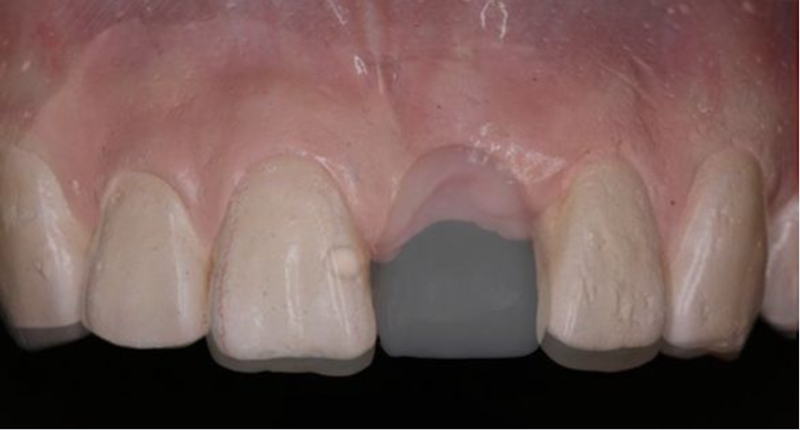

術(shù)前制取參考模型,排美學蠟型,實現(xiàn)以美學修復(fù)為導(dǎo)向的種植

使用U型管作為局部托盤,在石膏模型上,應(yīng)用聚醚硅橡膠進行印模

待硅橡膠凝固后,在印模中21缺牙區(qū)灌注阻射性材料(磷酸鋅或硫酸鋇/自凝牙托粉)

待阻射性材料凝固后,修整其邊緣及組織面

戴入患者口內(nèi),檢查U型管就位與石膏模型就位一致

檢查U型管及印模在口內(nèi)就位與石膏模型上一致

患者佩戴此U型管開合拍攝CBCT,其中可以獲得缺牙區(qū)修復(fù)體的切端及齦緣等信息